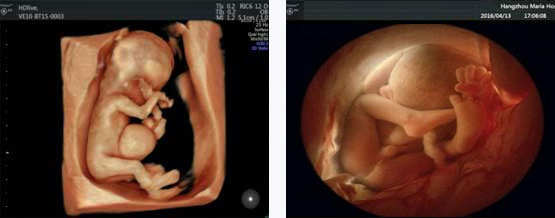

四维彩超能排查遗传性综合征等胎儿早期疾病。多角度观察宫内胎儿的生长发育情况,为早期诊断胎儿先天性体表畸形先天性心脏疾病提供科学依据。

四维彩超能够直观、立体地显示人体器官的三维结构以及动态,实时地观察立体结构,被广泛用于检查胎儿发育状况,立体观察胎儿在子宫内发育情况的同时,还能够清晰显示胎儿在子宫内的动态,让准爸妈们一起观看宝宝在妈妈肚子里的动作、神态,还可将这个过程制作成光碟保存,让宝宝能够拥有完整的0岁相册,留下珍贵的纪念。

四维彩超检查能够多角度观察胎儿在子宫内的发育状况,同时能够为早期诊断胎儿先天性体表畸形、先天性心脏疾病提供准确的科学依据。

四维彩超具备一整套成熟的胎心成像技术,支持从胎儿心脏结构到心功能的专业分析,是胎儿心脏检测评估领域的技术。双平面成像技术可实时观察胎心结构和血流变化,帮助临床医生及时作出诊断。

一般情况下四维彩超的检查时间是孕22-28周,这段时间检查,胎儿大小适合,羊水适中,胎儿活动度大,体表也比较丰满,有利于胎儿四维超声成像和畸形筛查,是合适的检查时期。